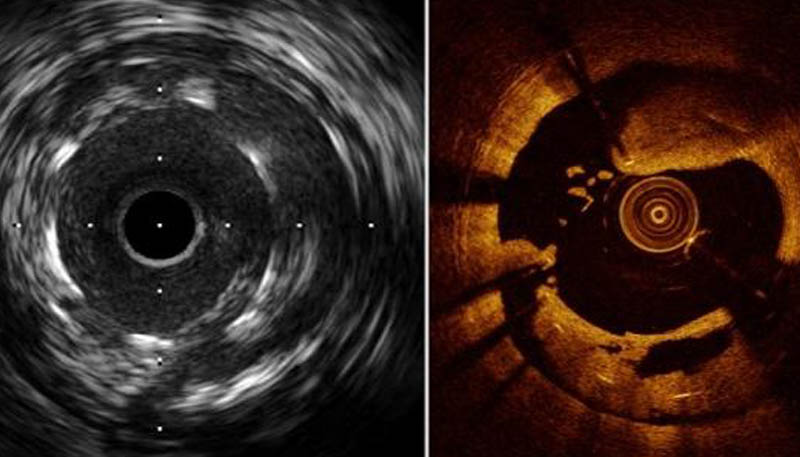

OCT & IVUS

OCT (Optical Coherence Tomography) is one of the ways that uses HD cross-sectional imaging.